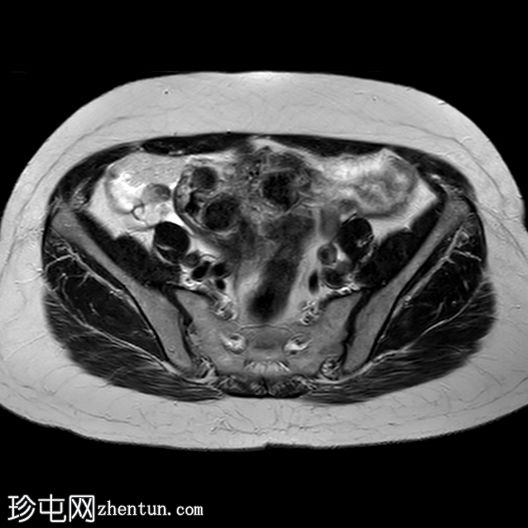

6个月前MRI检查

MRI

轴位

T2加权像

与既往CT同时进行的MRI检查显示子宫内有多发性T2低信号强度肌瘤,但在子宫右侧一个肌瘤内可见一处不均匀、中心高T2/囊性信号区。